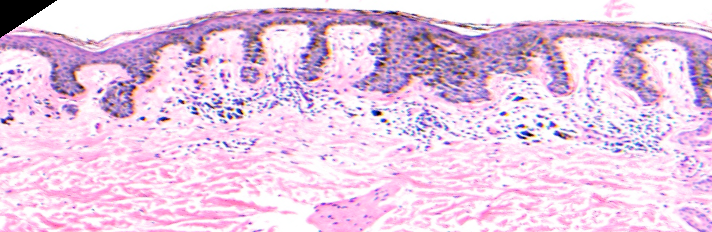

VA121: Left Mandibular Ramus, Junctional Melanocytic Nevus, Dysplastic

- Arrows indicate rete elongations

VA121: Left Mandibular Ramus, Adjacent, Normal